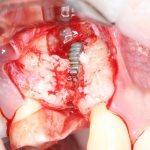

Забор костного фрагмента проводится с наружной косой линии с помощью ультразвукового пьезохирургического инструмента. Ничего сверхнового и супернеобычного тут нет, совершенно стандартная методика. С той лишь разницей, что молоток для этого используют только фашисты и только в гестапо использовать не нужно, всё делается усилием и ловкостью рук.

Нюансы начинаются с обработки принимающего ложа. Да-да, уважаемые друзья, одна из причин некроза блоков, их чрезмерной атрофии и прочих проблем — в отсутствии обработки принимающего ложа. Некоторые делают дырки, но правильнее и эффективнее поступить так:

то есть, просто снять слой кортикальной пластинки с участка, к которому будет фиксироваться костный блок. Почему? Читайте здесь>>.

Вторая особенность — мы не адаптируем и не обрабатываем костный блок invitro, а фиксируем его так, как есть:

после чего обрабатываем — доводим до окончательной формы альвеолярного гребня:

Далее, можем приступить к установке имплантатов. Разумеется. по хирургическому шаблону:

Последняя картинка даёт представление о том, какой объем костной ткани мы «нарастили».